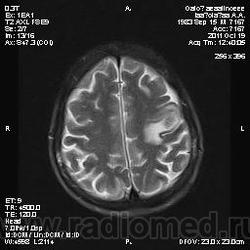

Молодой человек, жалуется только на головные боли и слабость в правой руке и ноге (около месяца).

Пациент полуасоциальный, нельзя исключить анамнез наркоманский....

ППН (включая ячейки пирамидок и сосцевидные отростки) тотально заполнены жидкостным компонентом...

Колеги, спасибо за высказывания. В данном случае про наркоманский анамнез указано не спроста... Есть мнение, что в этом лежит точка отсчета.... По поводу абсцесса и гематомы - не согласен; по поводу первого - нет соответствющей клиники, по поводу второго - не характерна локализация и сигнальные характеристики. Не буду томить общественность касательно собственного мнения. Есть две гипотезы, о которых думается в данном случае: прогрессирующая лейкоэнцефалопатия и новообразование... Но без контраста их не разрешить...

пожалуй "первое", но в отношении "второго"смущает "круглит" на вершине "воспалительной демиелинизации", который она (демиелинизация) так странно обходит...